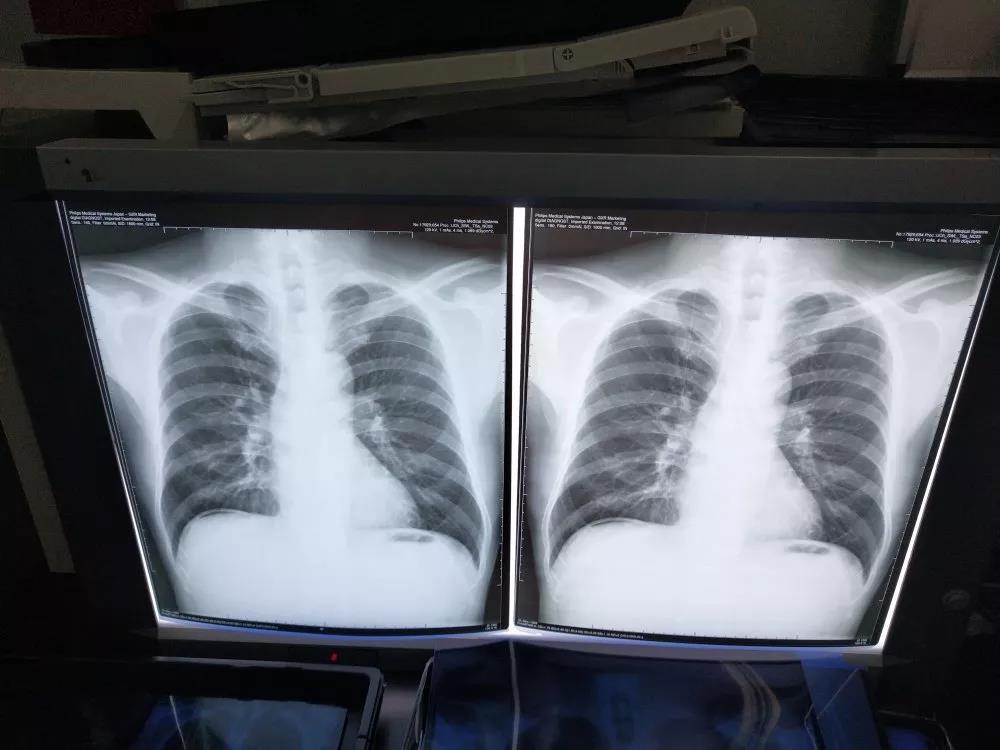

经了解,发热病人入院后,需要拍X光、CT等医疗影像检查,以排查新冠肺炎。随着新冠肺炎确诊及疑似病例的增长,对医疗胶片的需求大量增加。作为国内重要的医疗影像材料及技术的供应商,冠豪高新时刻关注全国防控工作的最新动态及防疫需求,在预判抗疫前线的需求后,紧急部署,立即安排生产技术人员加班加点保障医疗胶片涂料的生产。

2月5日,一批用于生产医疗胶片的涂料产品从冠豪高新发运,紧急驰援南通某医疗胶片生产企业。由于春节假期及疫情管控,物流运输不畅,冠豪高新与物流承运单位以高度的责任心和实际行动,协调各方,在物流公司的支持下,2月8日该批涂料成功送达客户工厂,该批材料可生产近50万张医疗胶片材料,保障了其医疗胶片的生产和交货,为新型冠病毒肺炎病例做医疗影像检查提供了物资保障。

医疗胶片生产企业使用冠豪涂料生产出来的胶片